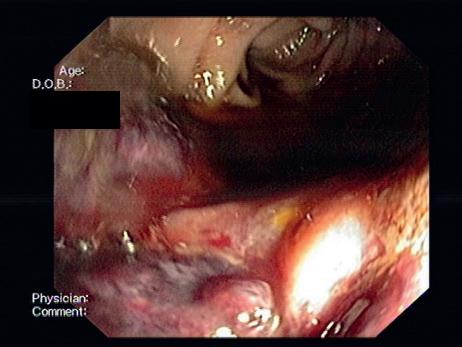

Figura 10.2.6 – ADC: A – Imagem de enteroscopia por cápsula a revelar formação globosa, congestiva, ulcerada e friável no jejuno proximal; B e C – BAE, que permitiu o esclarecimento etiológico e a realização de biópsias.